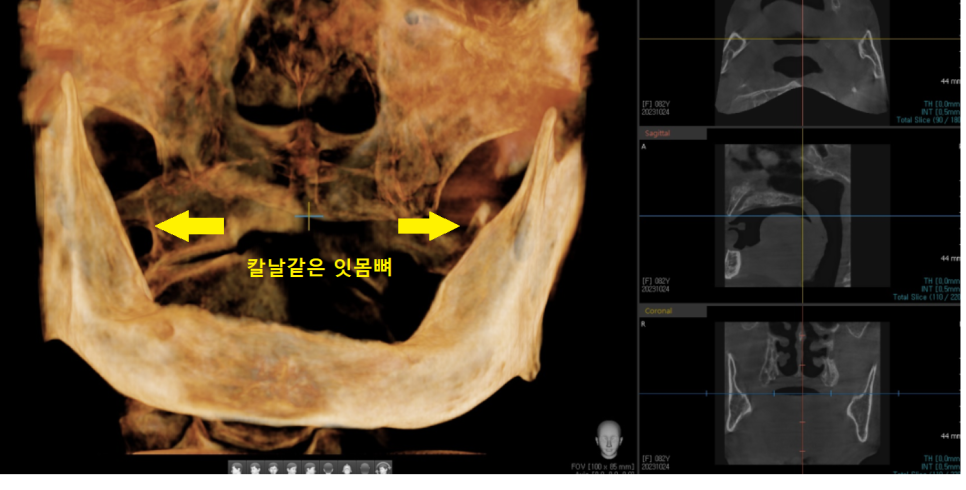

23.10.24

ct를 찍어보니 얇은뼈

얇다 못해 부러질 정도입니다.

먼저 ct를 찍어 남은 뼈의 양을 보았는데요.

구치부 어금니 쪽 잇몸뼈가 더 많아야 하지만

얇은뼈가 되어 앞니 쪽에만 뼈가 있는 상황이었습니다.

다행히 앞니 쪽은 임플란트가 가능하다는 분석이 나왔습니다.